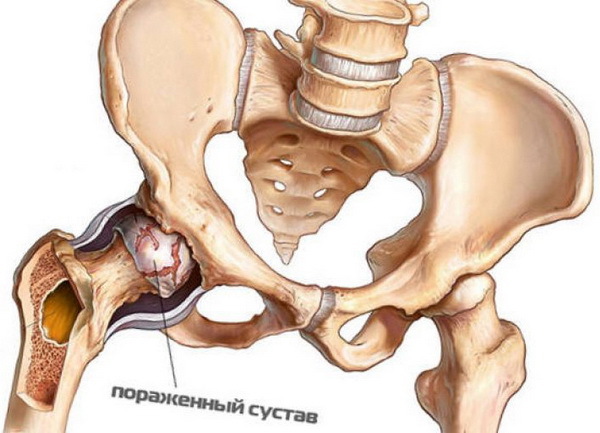

Некроз тазобедренного сустава: Фотографии и особенности лечения